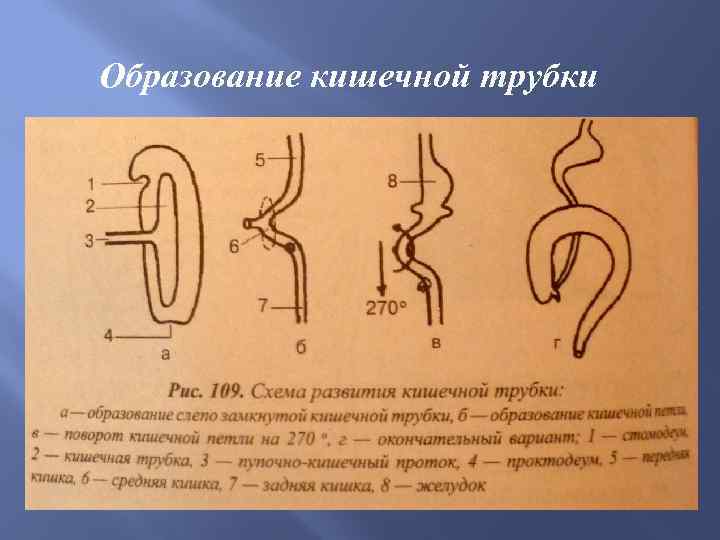

Образование кишечной трубки

Образование кишечной трубки